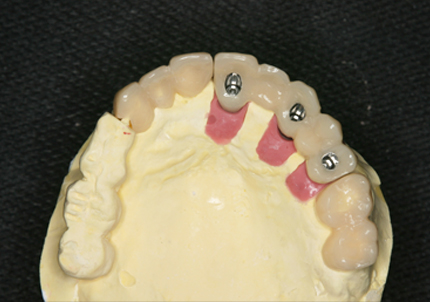

6.インプラントシリンダーテック作製

7.最終補綴作製(前歯部アバットメント装着)

8.ジルコニアフレーム、アバットメント試適

9.セラミック焼成

10.上顎補綴物装着(2008年12月)